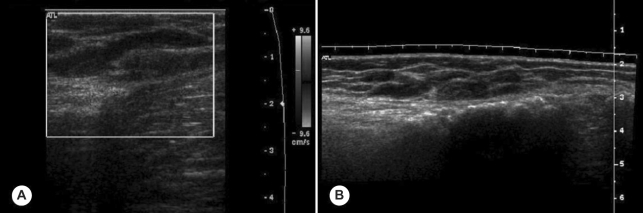

Fig. 1). Ultrasonography revealed subcutaneous hypoechoic elongated nodules and irregular intramuscular calcifications in the left lower leg antero-medially with slightly increased peripheral vascularity. Elongated and dilated superficial veins were also identified along the hypoechoic nodule and this showed compressibility at the same time (

Fig. 2Ultrasonography showing elongated and dilated superficial veins along the hypoechoic nodule (A), and oval, cystic lesions in subcutaneous tissue (B).